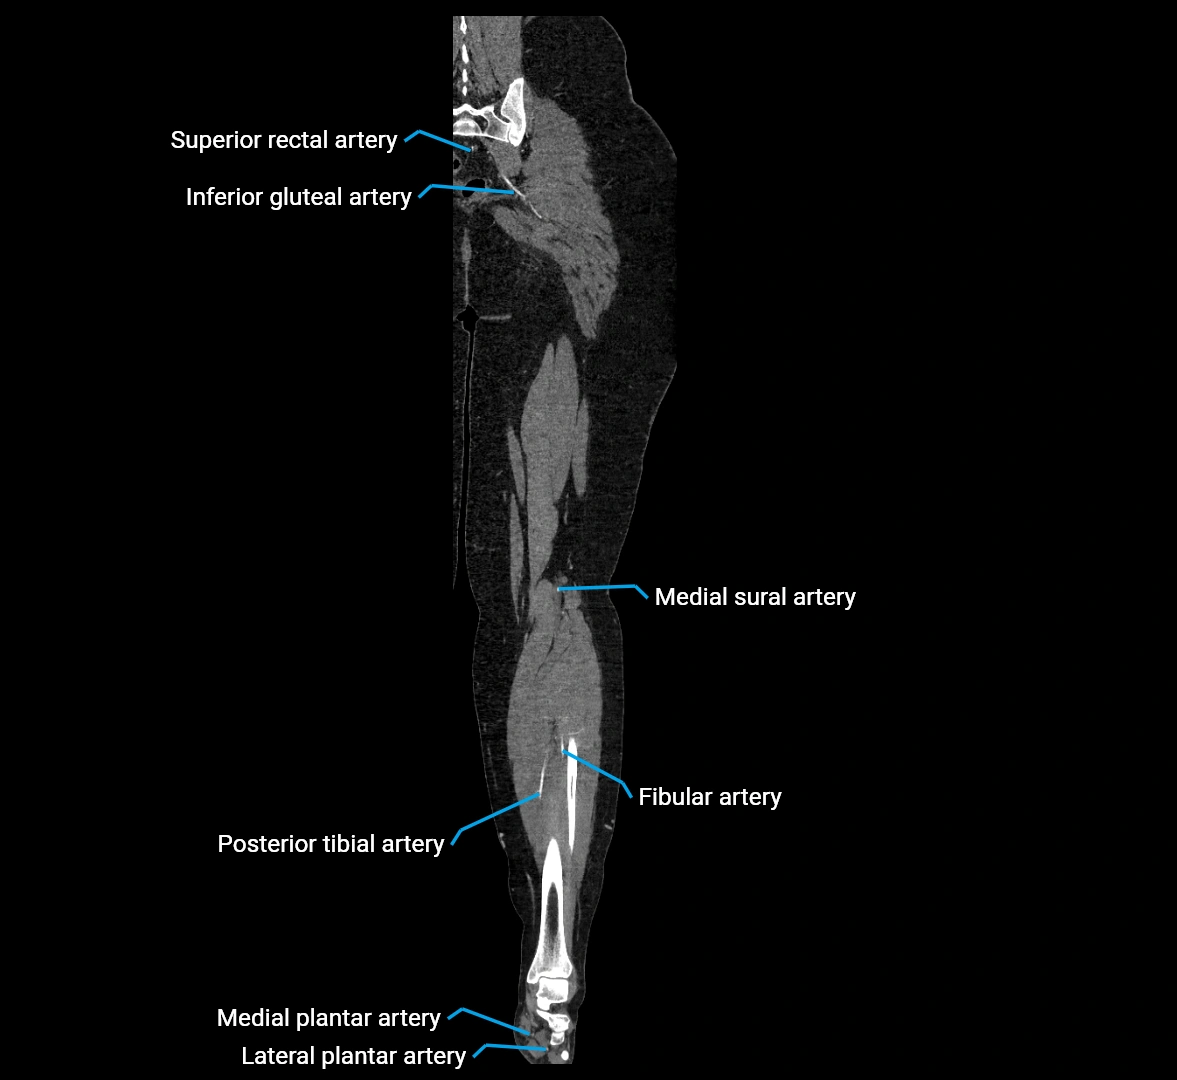

CT images

image

Contrast-enhanced CT (CTA):

• Gold standard for abdominal aortic imaging

• Provides excellent detail of lumen, wall, aneurysm, thrombus, and branch vessels

• Multiplanar and 3D reconstructions help in aneurysm measurement, stent graft planning, and dissection evaluation

• Detects acute rupture, traumatic injury, or occlusion with high sensitivity